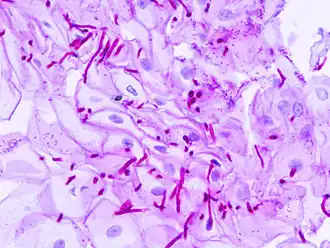

PAS reakce (Periodic Acid Schiff) je základní reakcí důkazu polysacharidů. Používá se jako jedna z barvicích metod při vytváření histologických preparátů, zejména v medicíně.

PAS reakce využívá vzniku aldehydů (dialdehydů) při oxidaci polysacharidů kyselinou jodistou. Vznikající aldehydy reagují s Schiffovým reagens (leukobáze fuchsinu[1]) a vytváří komplex s fialově červeným zbarvením.

Purpurově červeně budou zbarveny PAS pozitivní substance (glykogen, neutrální mukopolysacharidy a mukoproteiny). Modře jsou dobarvena jádra buněk.[2]